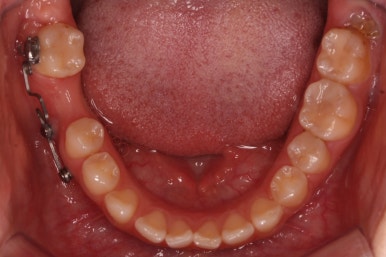

장치를 붙인 모습입니다.

개선을 하고자 하는 어금니에만 장치를 붙였고 다른 치아는 움직이지 않아야 하기 때문에 강한 지지대가 되어야 할 부분에 미니스크류를 식립했습니다.

치료 과정을 순차적으로 보겠습니다.

임플란트를 식립하기 위한 공간이 서서히 확보가 되어 가는 것이 보입니다. 어금니만한 사이즈로 공간이 확보가 되면 식립이 이뤄지죠.